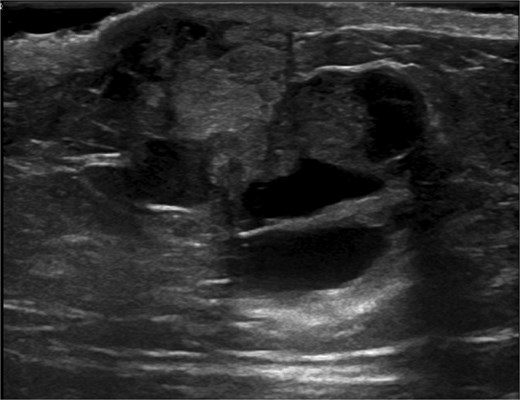

Ultrasound-guided core needle biopsy of the mass showed dissociated fragments of cribriform-like and papillary-like carcinoma (Figs 3 and 4).

Ultrasound of retroareolar area of palpable concern – first view.